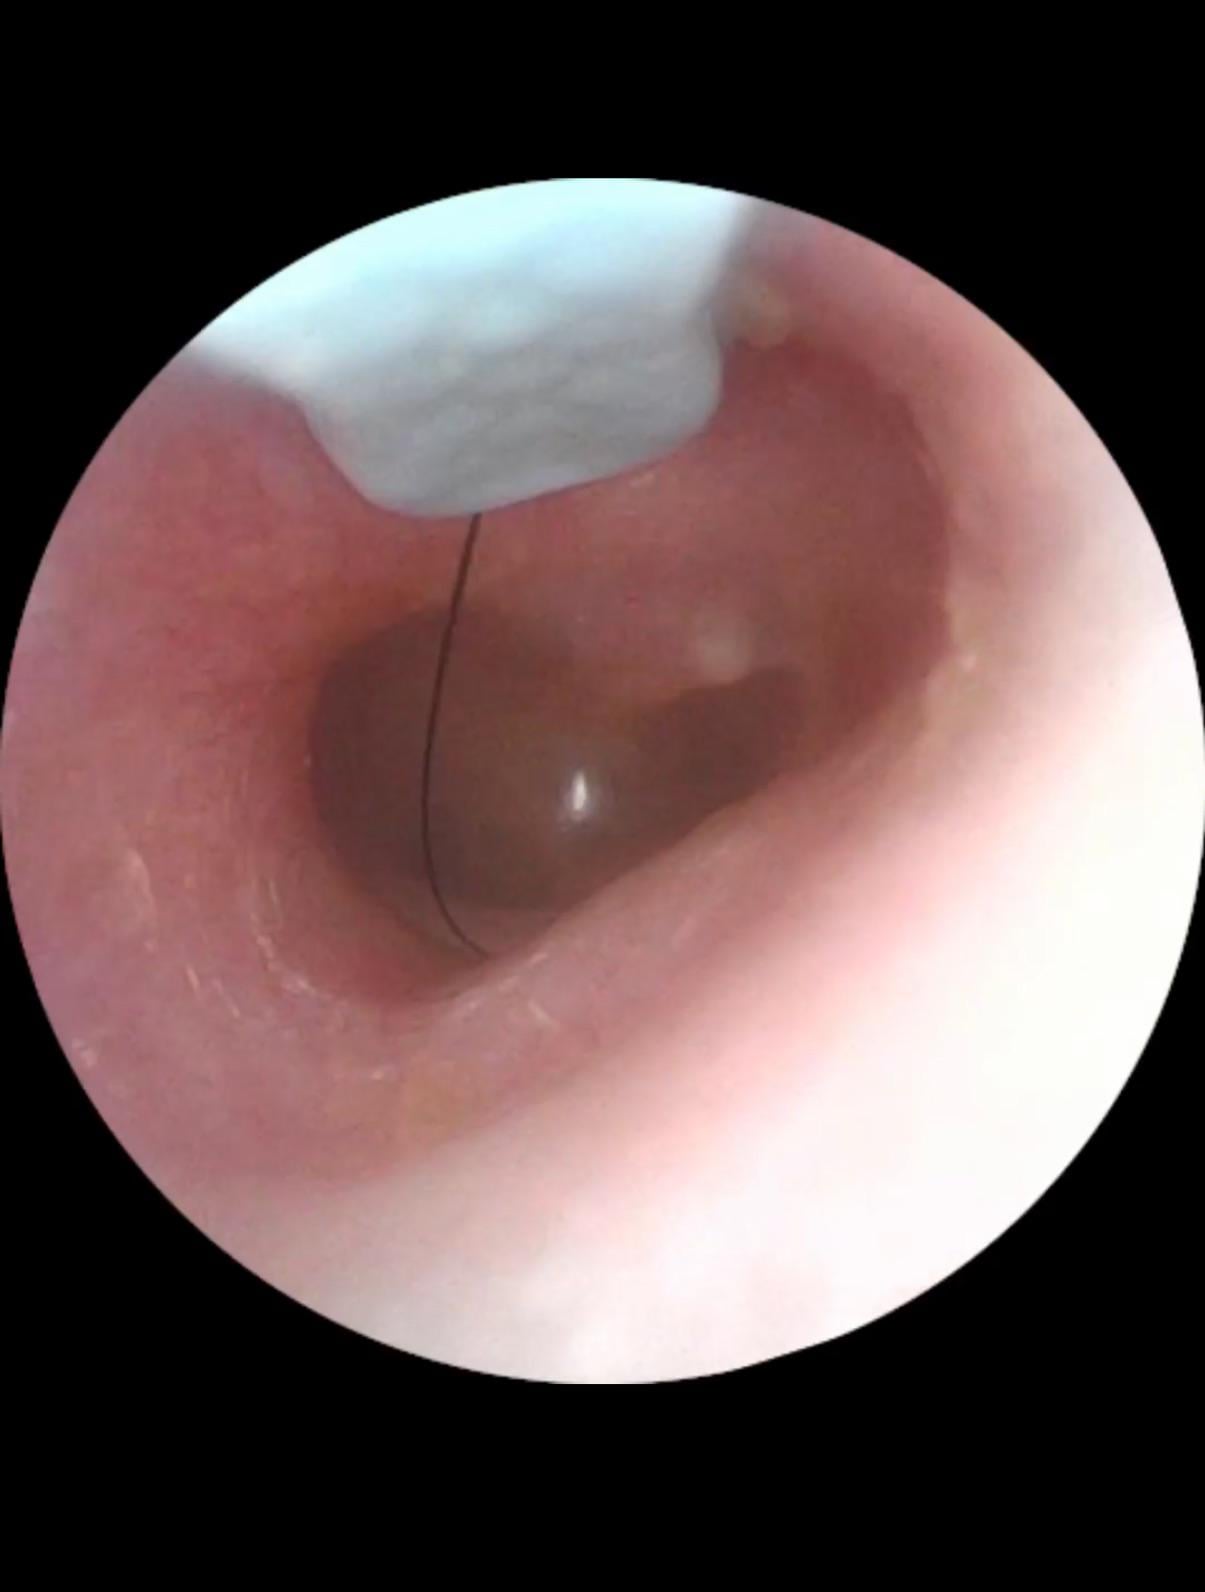

- I had this camera in my ear for 4 seconds, snapped a pic for the doc, I know not to go any further or else I could damage my eardrums. Super super aware*

I also have low income insurance and apparently this is only a job for an ENT with a micro suction appliance. It’s been 2 weeks since I’ve had a peaceful sleep.